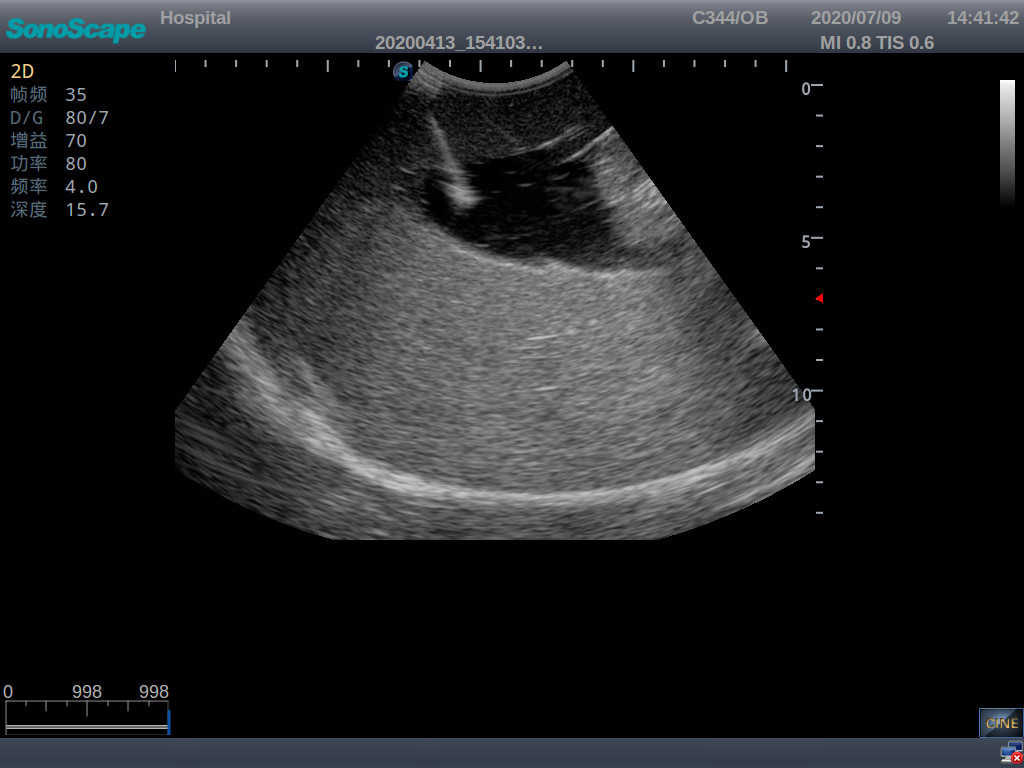

· High-quality ultrasound images for users to recognize 22-week fetus, placenta, placenta, umbilical cord and amniotic fluid

· Compatible with various real ultrasound machines